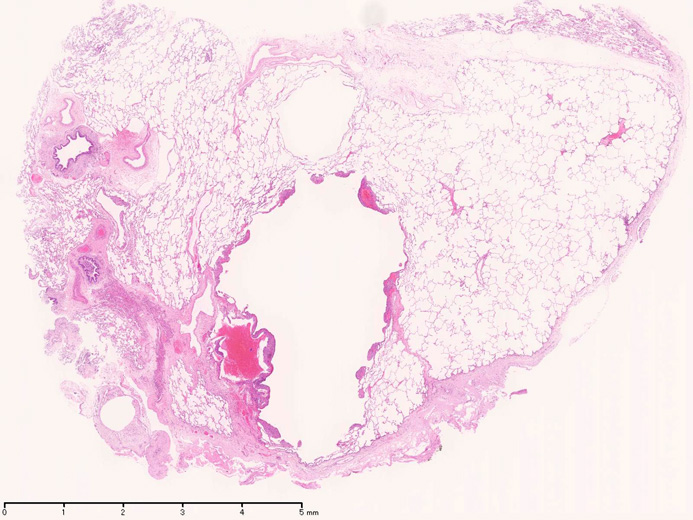

LAMの組織病理

Virtual Slides---> 肺VATS組織[1], 肺VATS組織[2]

LAMの肺病変

嚢胞周囲または肺血管, リンパ管, 細気管支にそうLAM cellの浸潤, 集簇を特徴とする。LAM cellには2種類が認められ, 小型紡錘形細胞と細胞質の豊富な類上皮様細胞があり, 紡錘型は主に集簇巣の中心に存在し増殖能が高い。 類上皮様LAM cellは辺縁部に多く, 増殖能は低いがHMB45を強く発現している。

嚢胞形成はLAM cellの増殖と関連しており, 細胞が産生するmatrix metalloproteinases(MMPs)による組織破壊によるらしい。